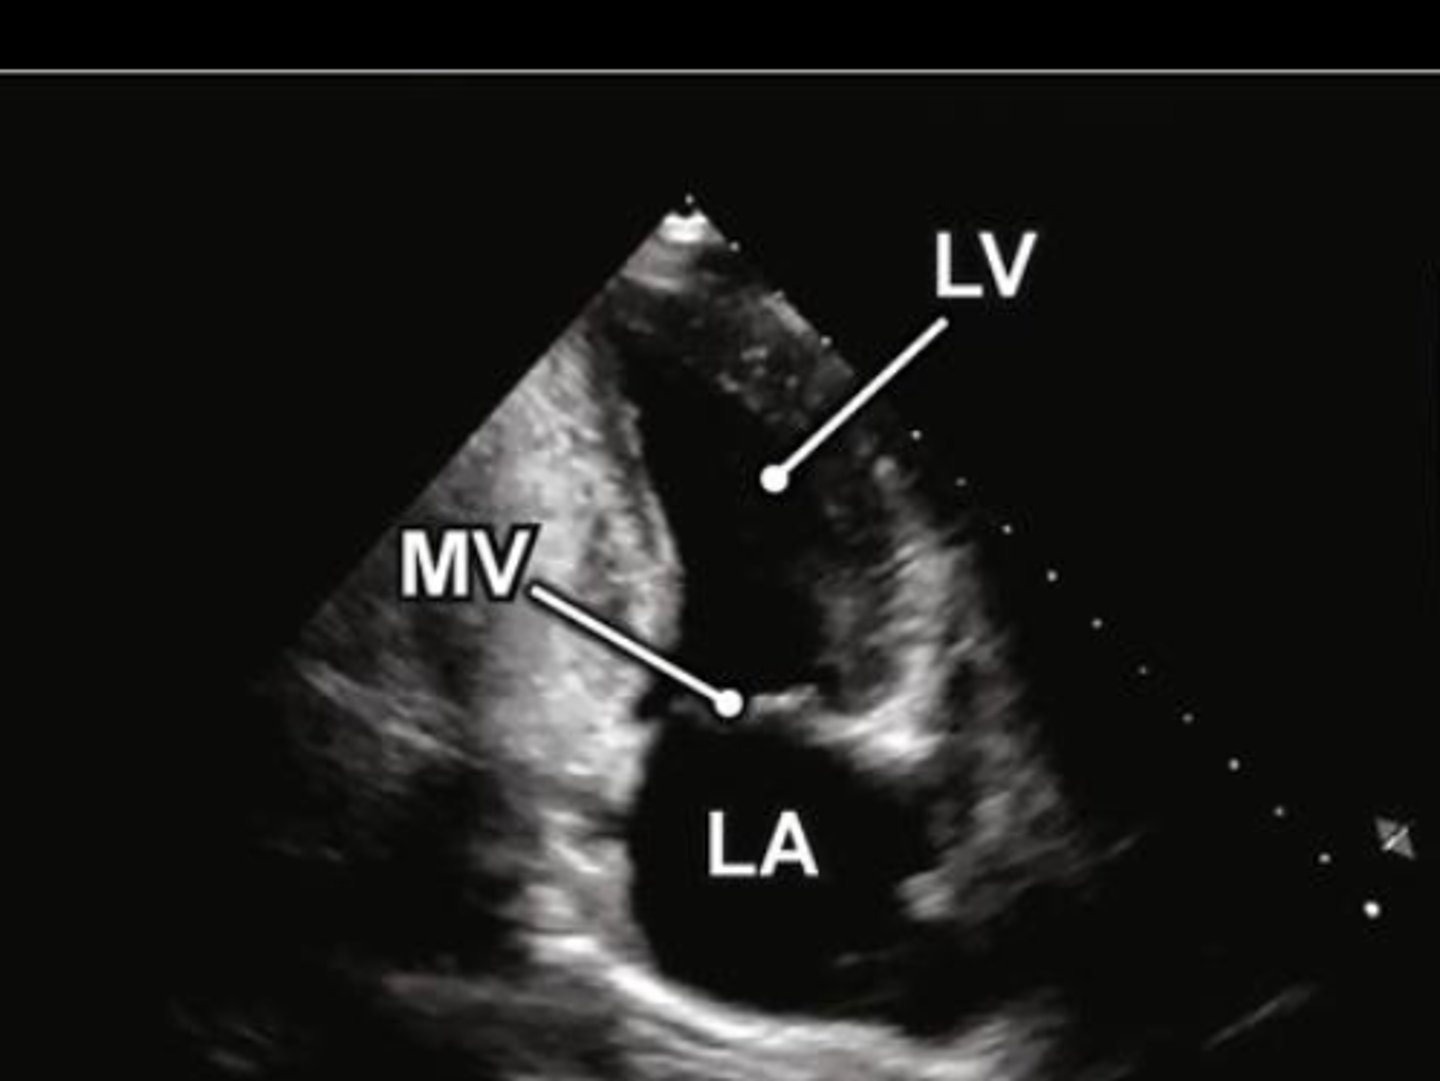

A2 is used to visualize _____

MV